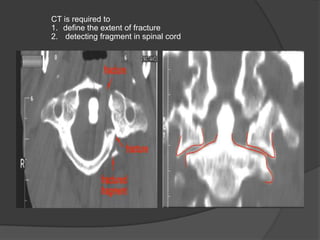

CT is required to

1. define the extent of fracture

2. detecting fragment in spinal cord